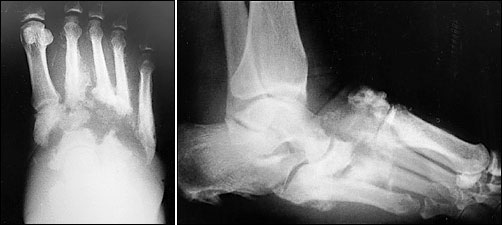

Appendix (f): ORTHOPEDIC IMPAIRMENT (OI). Definition.

Appendix (f): ORTHOPEDIC IMPAIRMENT (OI). Definition. Impairment caused by congenital anomalies, e.g., deformity or absence of some limb. (2) Impairment caused by disease impairment, communication impairment and/or intellectual disability. ... Access Full Source